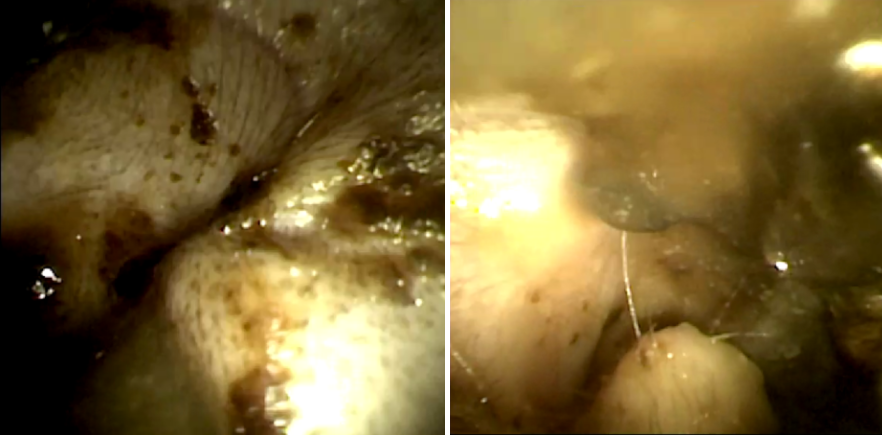

[고양이 귀 내시경 수술]

경기동물의료원 에서는 고양이 외이염이 발생한 부위에 대해 안전하게 시술을 집행하였습니다.

고양이 귀 내시경 상에서 검은 귀지와 더불어 농성 삼출물이 다량 관찰됩니다.

검은 귀지들 및 염증성 삼출물들을 내시경을 사용해 플러싱 진행하였고,

고양이 외이염의 원인이 되고 있는 이도 내 신생물을 확인할 수 있었습니다.